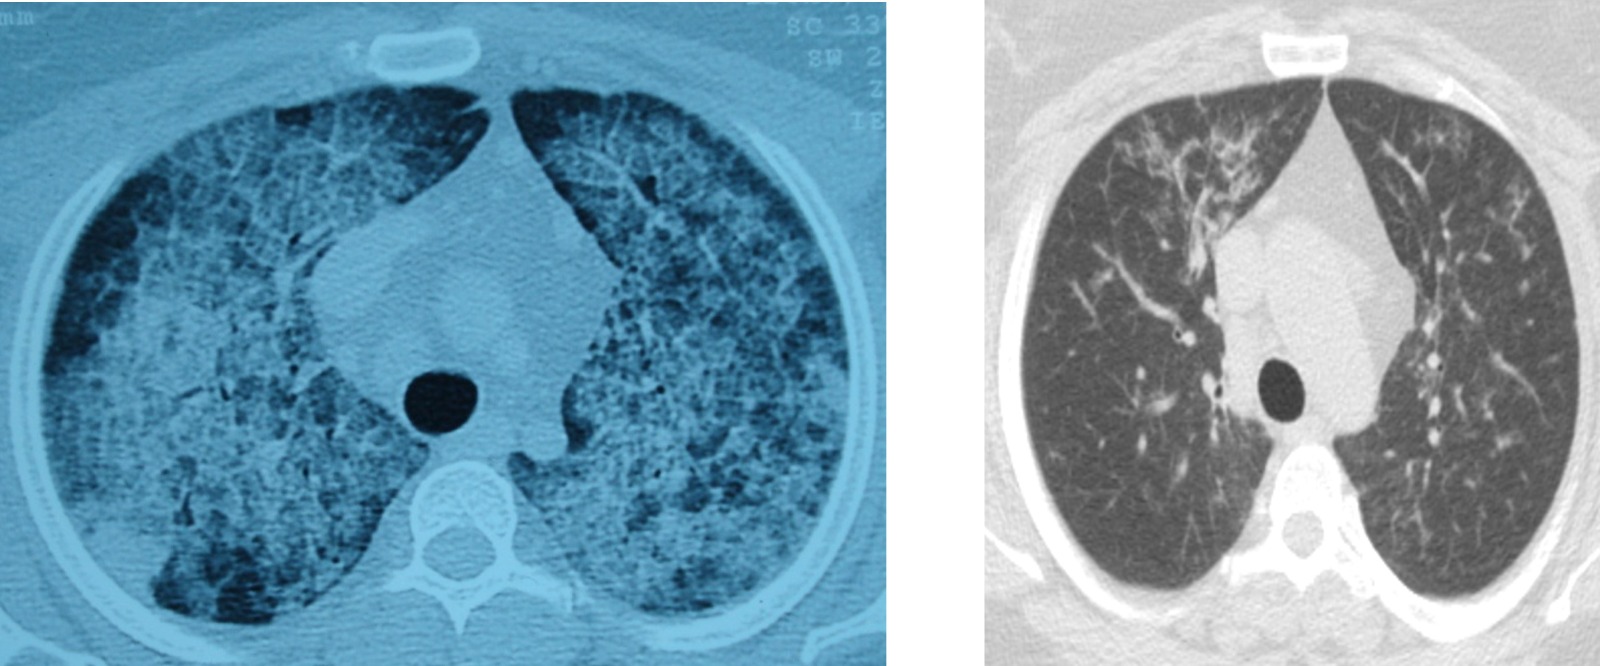

Hastalığın, kişinin kendi yağ ve proteinlerinin temizlenmesiyle görevli hücrelerdeki sorun nedeniyle akciğerlerdeki hava keseciklerinin birikmesi sonucu ortaya çıktığını aktaran Ergur, belirtilerin nefes darlığı, yorgunluk ve aşırı halsizlik olduğunu kaydetti.

Ergur, hastalığın çoğu zaman astımla karıştırıldığını, tanının ancak ileri tetkiklerle konulabildiğini ifade etti.